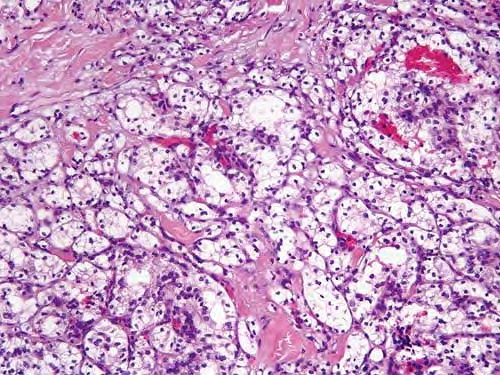

metastasis